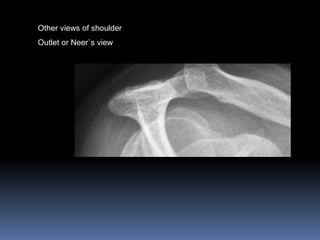

Other views of shoulder

Outlet or Neer`s view